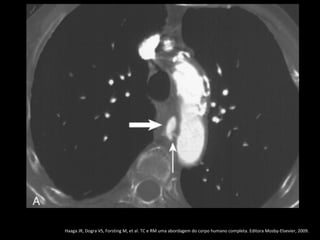

Ruptura: extravazamento do contraste e hemotórax

Haaga JR, Dogra VS, Forsting M, et al. TC e RM uma abordagem do corpo humano completa. Editora Mosby-Elsevier,

2009.